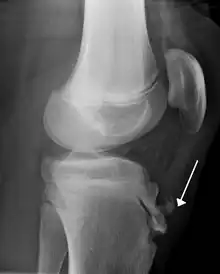

| Lateral view X-ray of the knee demonstrating fragmentation of the tibial tubercle with overlying soft tissue swelling. | |

Risk factors include overuse, especially sports which involve frequent running or jumping.[3] The underlying mechanism is repeated tension on the growth plate of the upper tibia.[3] Diagnosis is typically based on the symptoms.[3] A plain X-ray may be either normal or show fragmentation in the attachment area.[3]